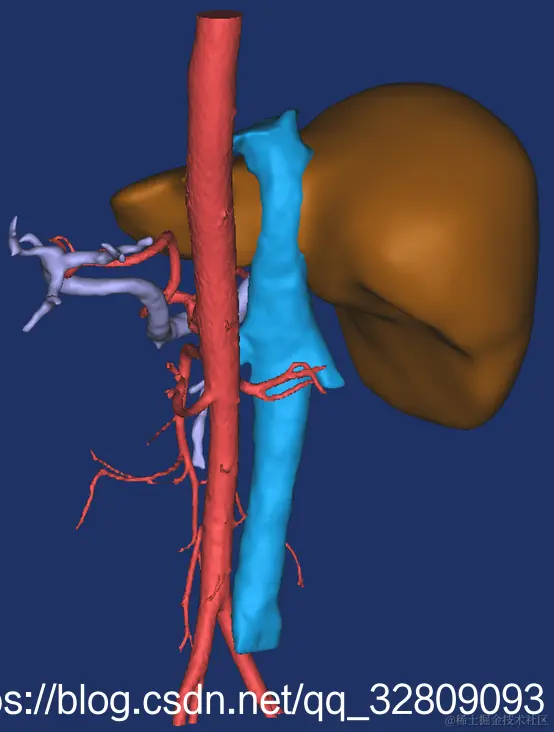

最后建模出来的效果:

正面图(肝脏+动脉+门静脉+腔静脉)                                反面图                                                          透视图